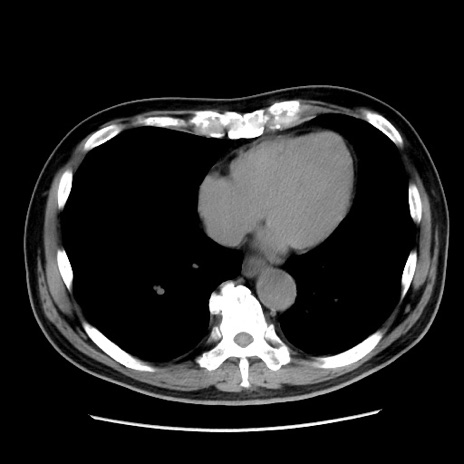

症例16(横断像)

【症例】 70歳代男性

【主訴】 腹痛、嘔吐

【現病歴】 約1ヶ月前より間欠的に腹痛と嘔吐あり、当院消化器内科を受診したところCTで多発する肝臓のLDAを指摘され、精査中であった。以降は消化器症状は安定していたが、2日前より嘔気と腹痛があり、同日より排便・排ガスが消失した。改善認めず、 本日、救急外来を受診した。

【既往歴】 大腸ポリープ切除後。

【身体所見】意識清明・会話良好、BT 36.3℃、BP 127/80mmHg、 P 80bpm、腹部:膨満あり、平坦・軟、上腹部正中および下腹部正中に圧痛あり、反跳痛なし、筋性防御なし。

【データ】WBC 7200、CRP 0.77